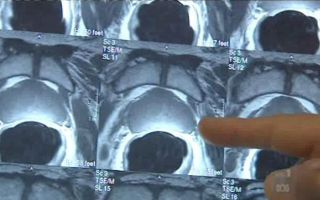

Prostate cancer drug added to Pharmaceutical Benefits Scheme

A pill to treat men with prostate cancer that can no longer be stopped by low testosterone levels will be made available...